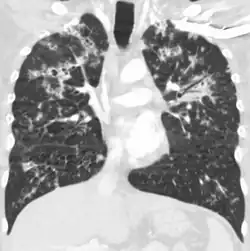

Miliary tuberculosis is a form of tuberculosis that is characterized by a wide dissemination into the human body and by the tiny size of the lesions (1–5 mm). Its name comes from a distinctive pattern seen on a chest radiograph of many tiny spots distributed throughout the lung fields with the appearance similar to millet seeds—thus the term "miliary" tuberculosis. Miliary TB may infect any number of organs, including the lungs, liver, and spleen.[2]

Testing for miliary tuberculosis is conducted in a similar manner as for other forms of tuberculosis, although a number of tests must be conducted on a patient to confirm diagnosis.[3] Tests include chest x-ray, sputum culture, bronchoscopy, open lung biopsy, head CT/MRI, blood cultures, fundoscopy, and electrocardiography.[9] The tuberculosis (TB) blood test, also called an Interferon Gamma Release Assay or IGRA, is a way to diagnose latent TB. A variety of neurological complications have been noted in miliary tuberculosis patients—tuberculous meningitis and cerebral tuberculomas being the most frequent. However, a majority of patients improve following antituberculous treatment. Rarely lymphangitic spread of lung cancer could mimic miliary pattern of tuberculosis on regular chest X-ray. [14]

A case of miliary tuberculosis in an 82-year-old woman: